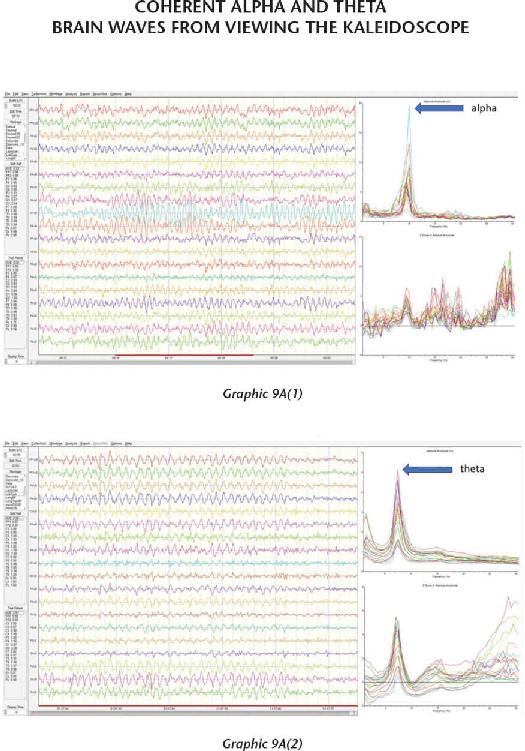

We have thousands and thousands of brain scans that prove those changes were not just imagined in their minds but actually took place in their brains. Several of the students we measured accomplished those changes within four days (the length of our advanced workshops). The scientific teams I’ve assembled have taken brain scan recordings using quantitative electroencephalogram (EEG) measurements before and after workshops as well as real-time measurements during the meditations and practices themselves. I was not only impressed with the changes, but shocked by them—they were that dramatic.

The brains of our students function in a more synchronized and coherent fashion after participating in the advanced retreats around the world. This increased order in their nervous systems helps them get very clear about a future they can create, and they are able to hold that intention independent of the conditions in their external environment. And when their brains are working right, they are working right. I will present scientific data that shows how much their brains improved in just a few days—which means you can do the same for your brain.

Chapter 8 shares one of the other favorite activities we do at our advanced workshops: combining a kaleidoscope with videos called Mind Movies that our students make of their future. We use the kaleidoscope to induce a trance because when you are in trance you are more suggestible to information. Suggestibility is your ability to accept, believe, and surrender to information without any analysis. If you do this properly, it is indeed possible to program your subconscious mind. So it makes sense that when you use the kaleidoscope to change your brain waves—with your eyes open instead of closed in a meditation—you can lower the volume of the analytical mind to open the door between the conscious mind and the subconscious mind.